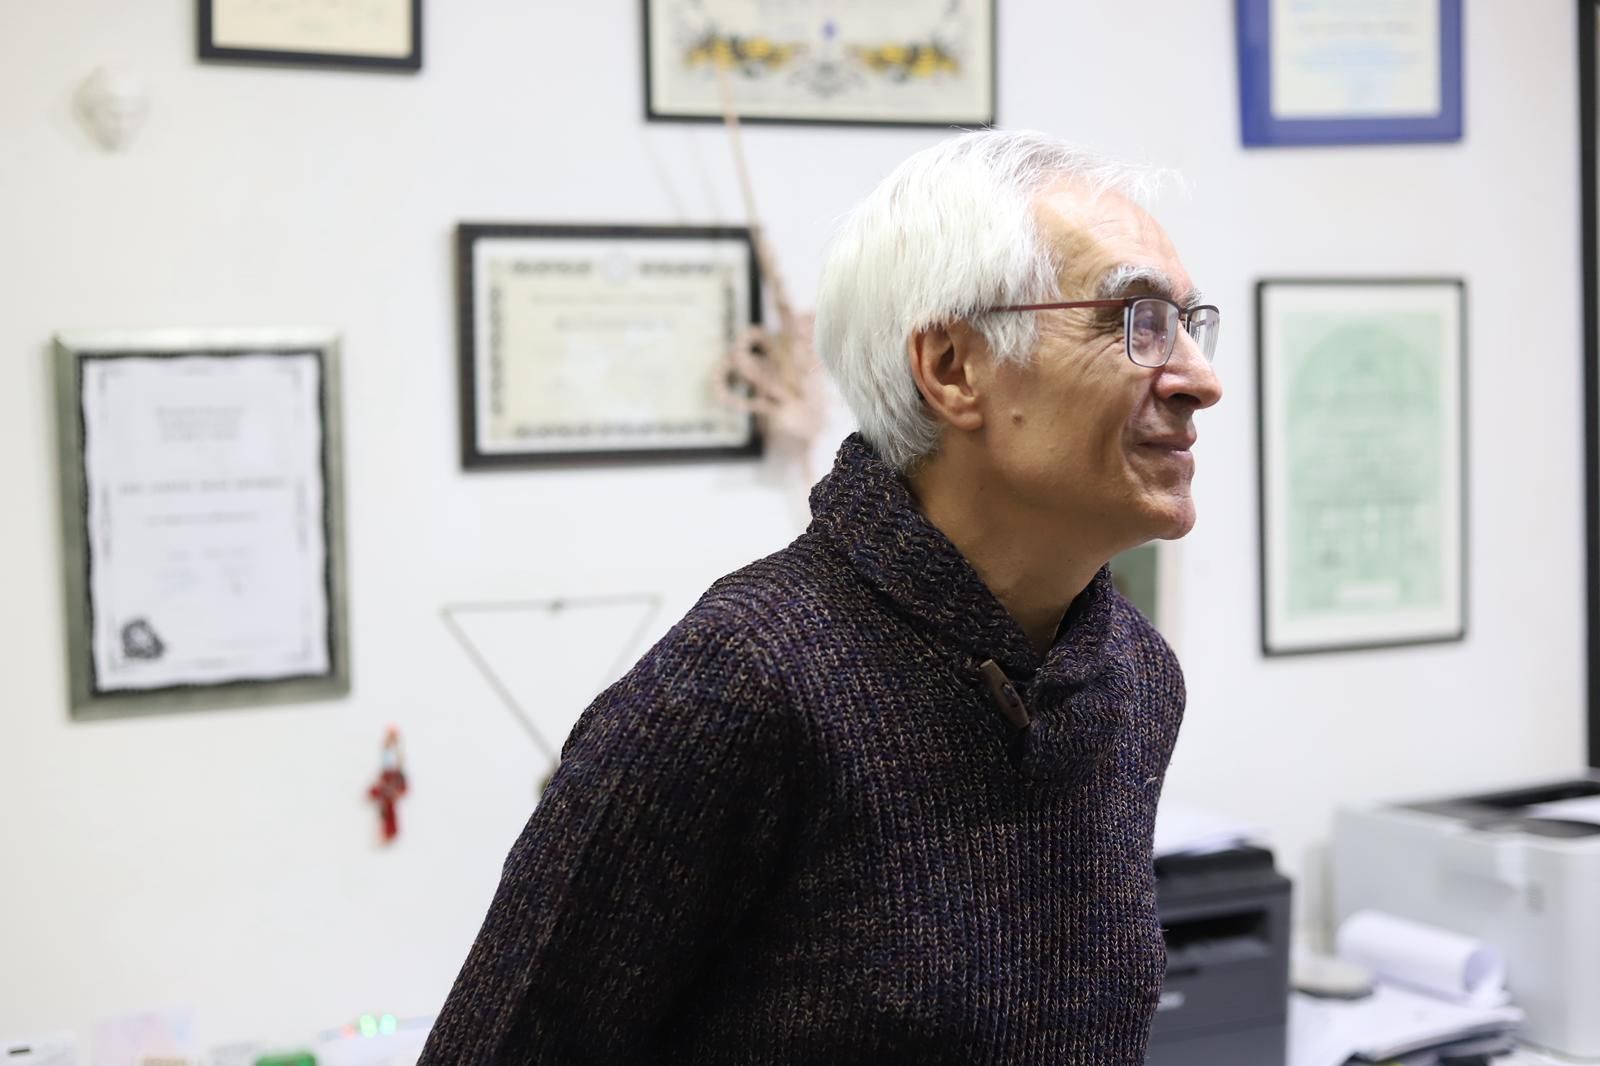

El profesor de neurooncología en la Facultad de Medicina David Geffen de la UCLA y coautor principal del estudio, el doctor Timothy Cloughesy, asegura que la disponibilidad de un tratamiento que permite a los pacientes pasar períodos más largos entre la quimioterapia y la radiación podría tener un gran impacto.

"Siempre nos preocupan los efectos retardados de la radiación. Tener la capacidad de posponer la radioterapia en el cerebro con una terapia efectiva es realmente fundamental y muy significativo para esta población de pacientes", declara.